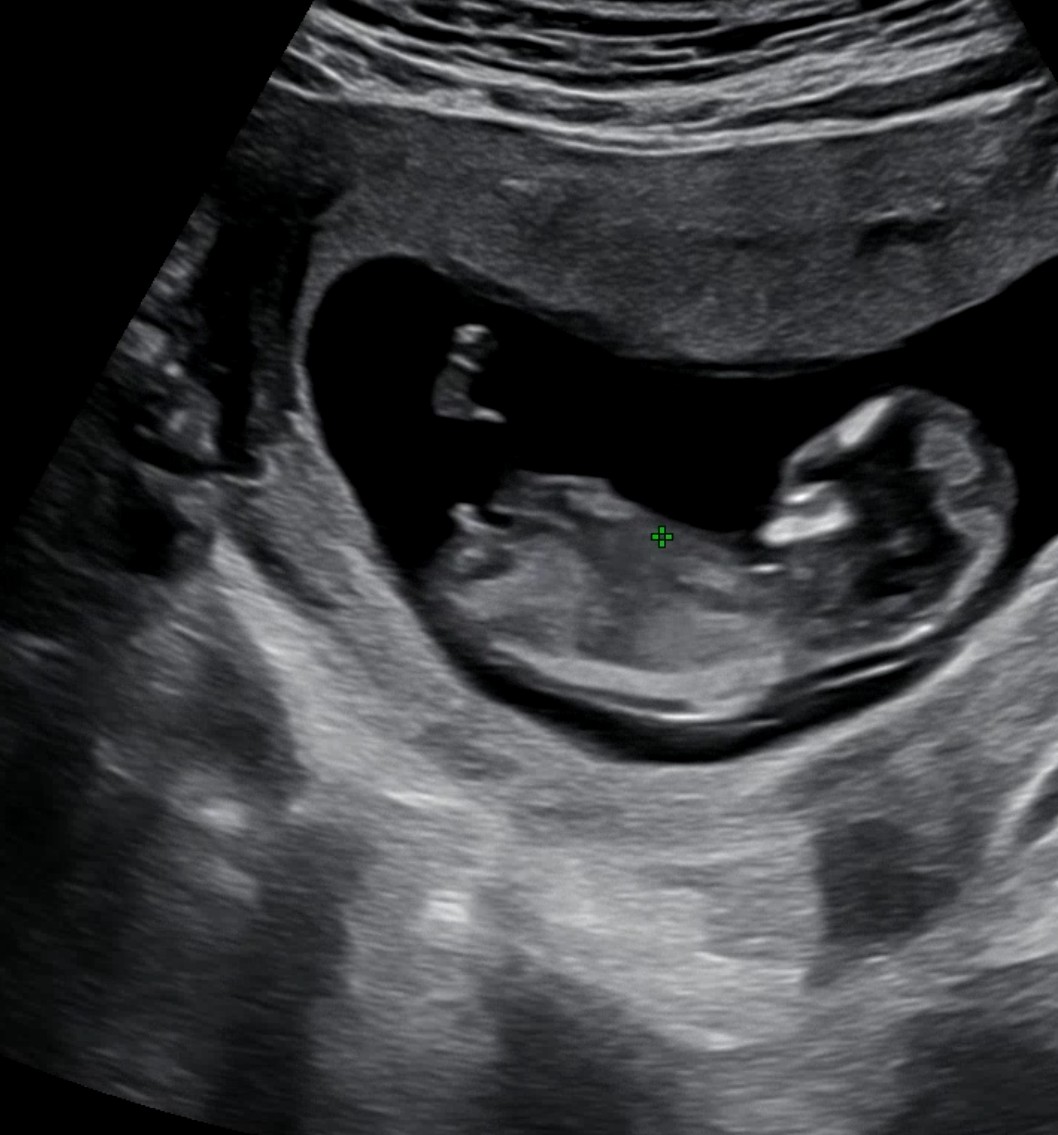

12주 초음파사진입니다 아들각도일까요?

12주 초음파에요 보이는 각도모양이 아들각도일까요?